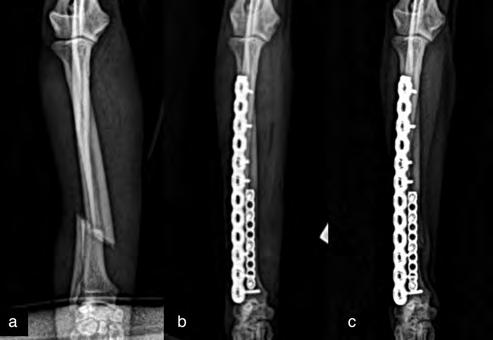

Después de la cirugía se analizaron las radiografías postoperatorias, realizándose las mismas mediciones que en la planificación, y observándose cómo los valores obtenidos tras la cirugía se correspondían con los valores planificados (Fig. 5). Se colocó un vendaje postoperatorio sencillo durante 14 días, para evitar la manipulación del área quirúrgica por parte de la pa-

Figura 5. Proyecciones radiográficas craneocaudal y mediolateral posquirúrgicas. Las radiografías muestran el resultado tras la cirugía.

Figura 7. Proyecciones radiográficas (A) craneocaudal y (B) mediolateral a los 4 meses de la cirugía. Las imágenes muestran la avanzada consolidación de la ostectomía.